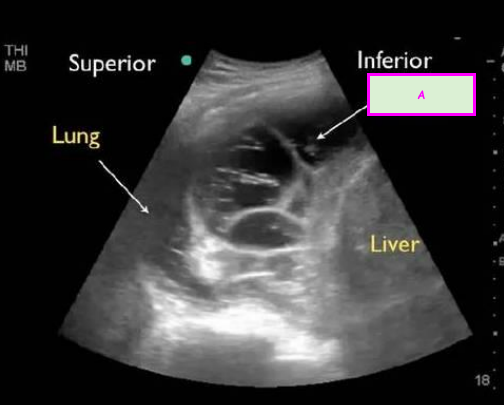

1

Q

This image shows an ultrasound of the lung.

What is A? [1]

A

Pleural effusion